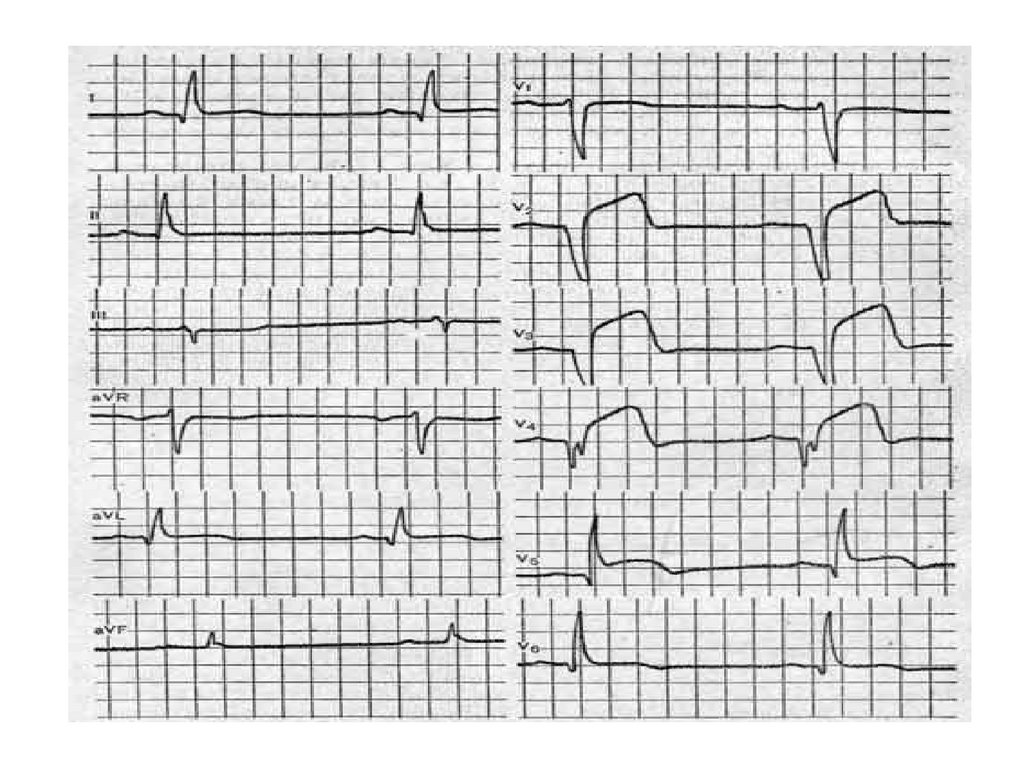

WPW синдром

WPW-синдром

• Тип А: ЭОС вправо, признаки БПНПГ

• Тип В: ЭОС влево, признаки БЛНПГ.

• Тип АВ: ЭОС влево, признаки блокады

ПНПГ.

127.

WPW-синдром тип А

128.

WPW-синдром тип В